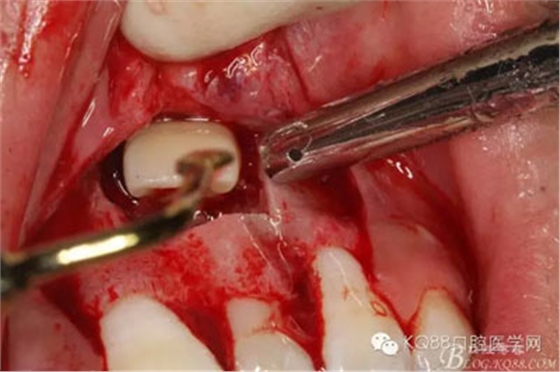

圖9.超聲骨刀去除隆起的骨壁

圖10.形成梯形骨縫

圖11.掀開骨壁。摘除牙瘤及牙囊組織

圖12.摘除囊壁后,暴露出21的切端